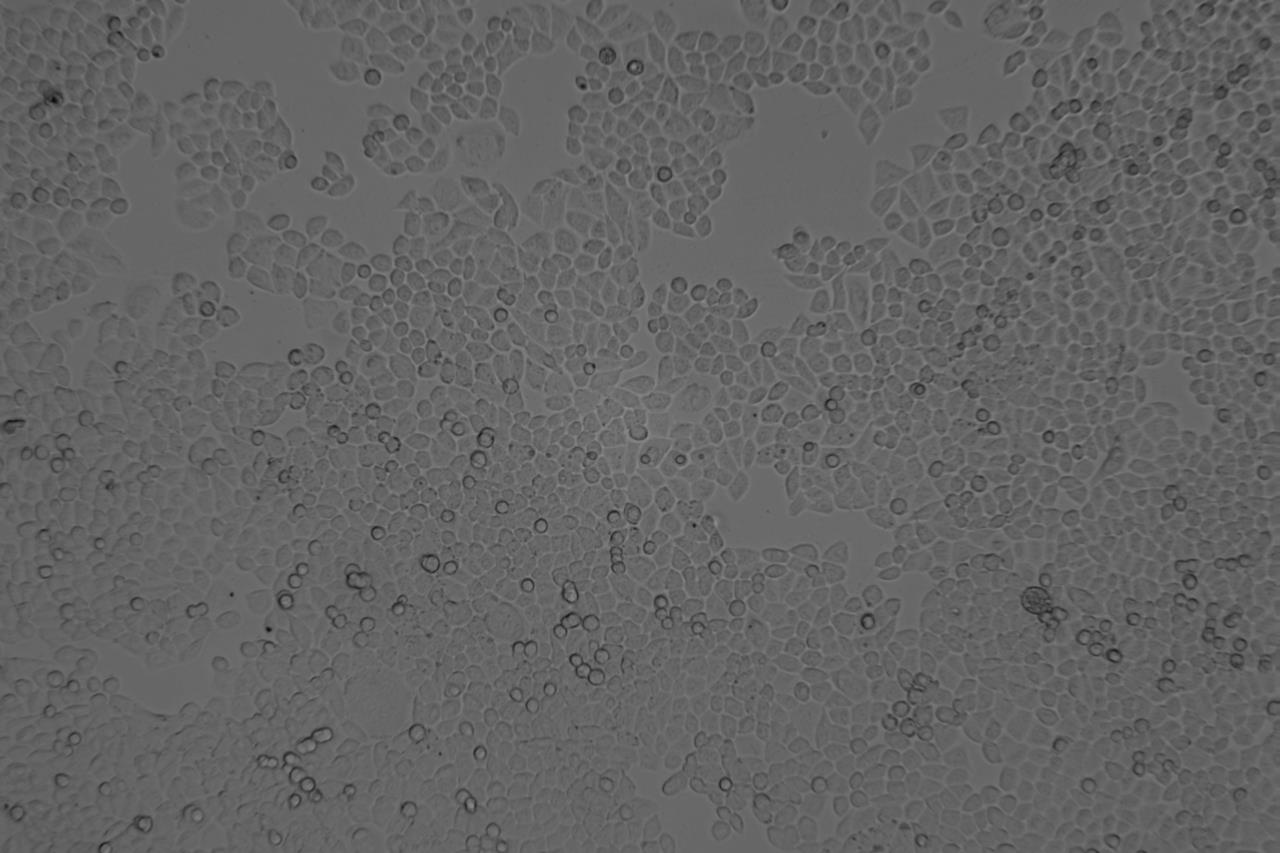

HCT-8/FU 人結(jié)腸癌氟尿嘧啶耐藥株

細(xì)胞名稱:HCT-8/FU 人結(jié)腸癌氟尿嘧啶耐藥株(含STR鑒定)

1、 來源:人 肺癌

2、 形態(tài):上皮細(xì)胞樣 貼壁

A.90%RPMI-1640+10%胎牛血清+10000ng/ml 氟尿嘧啶。

B.培養(yǎng)條件:37.0C  carbon dioxide(CO2),5%